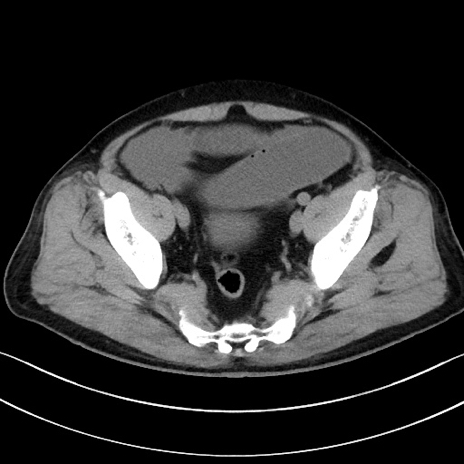

冠状断像

【症例】70歳代男性

【主訴】腹痛

【現病歴】今朝から腹痛あり。全体的に痛い。特に左上の方。排ガスが今日はない。冷や汗が出る。

【既往歴】直腸癌術後

【身体所見】左側腹部〜上腹部に圧痛あり。腹膜刺激症状明らかなではない。軽度反跳痛。左下腹部に術後瘢痕あり。

【データ】WBC 7700、CRP 0.02